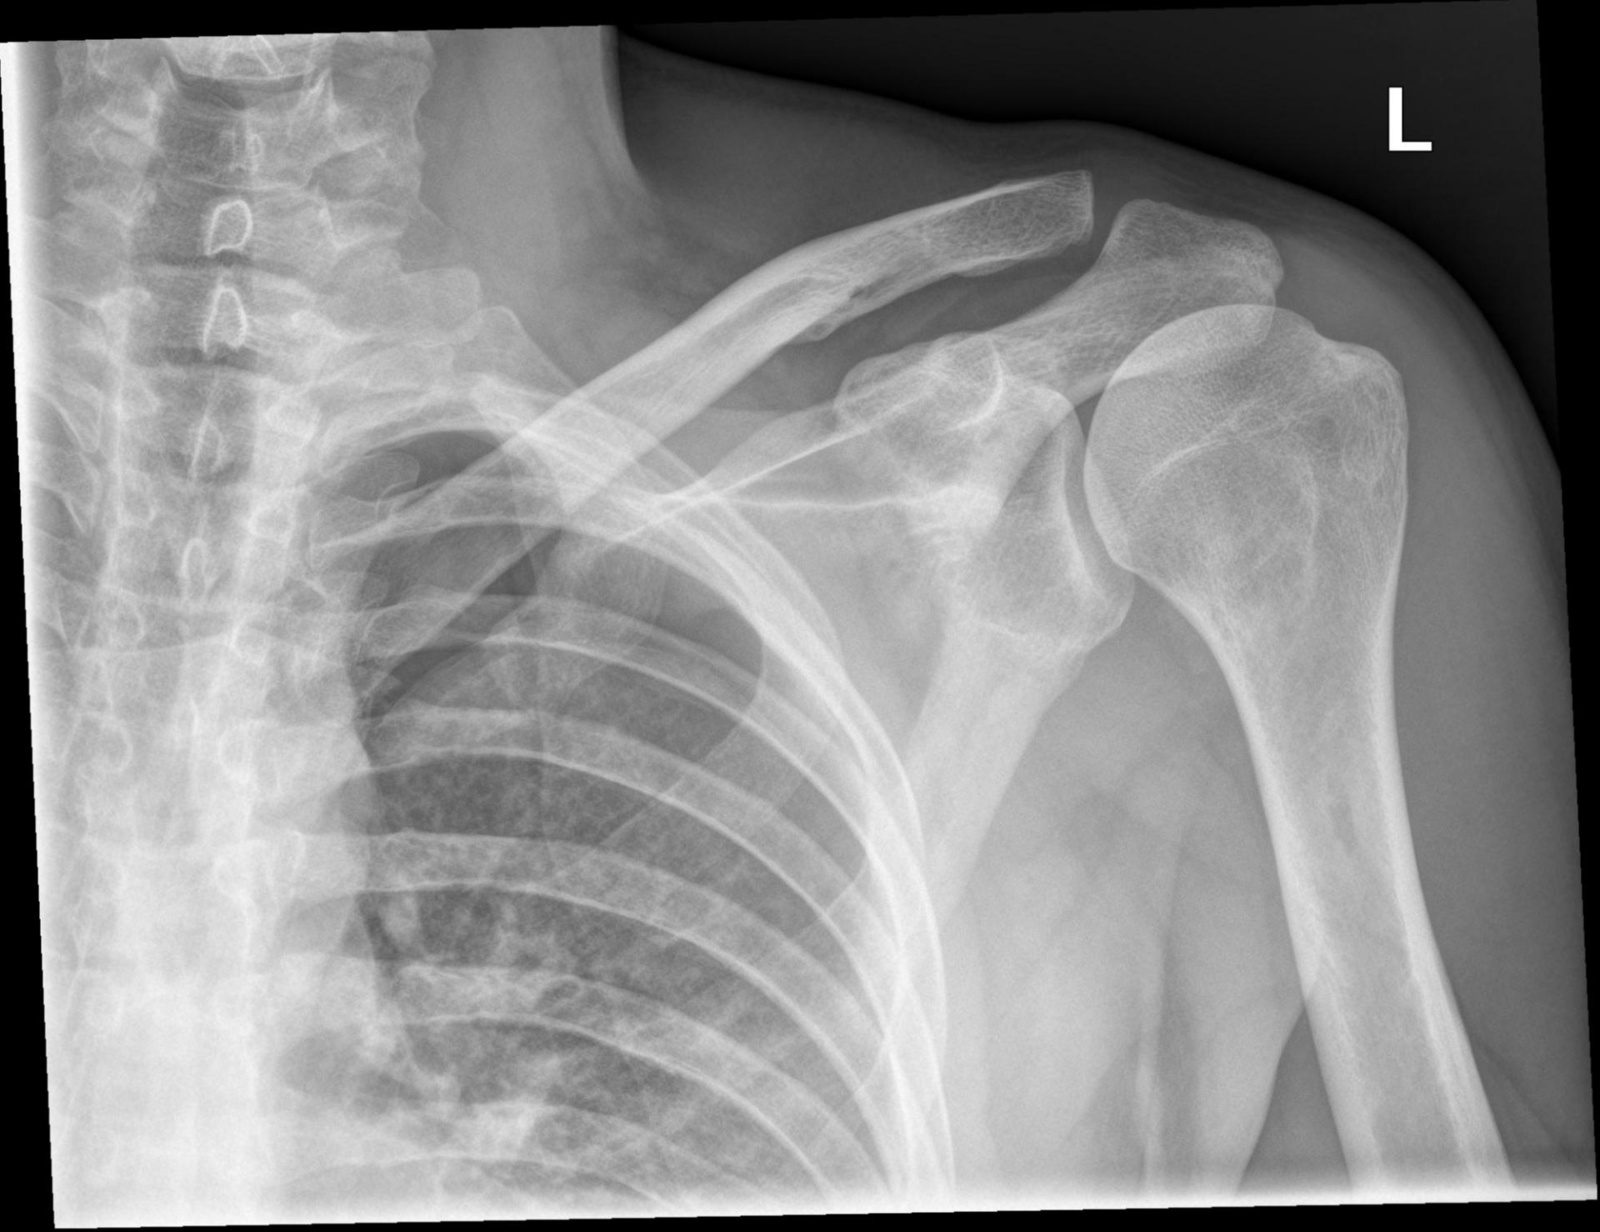

Чаще всего привозят трупы с черепно-мозговыми травмами, переломами грудной клетки и кистей. Часто травмируются чуть ли не все кости в кисти, так как рука соскальзывает с руля и летит в приборную панель. При аварии тело обычно «едет вверх», так что у водителя ломаются ноги, колени, голени. При сильных фронтальных ударах страдают плечевые кости.

Если водитель не был пристегнут, то в серьезной аварии он подписал себе смертный приговор. Тела таких автолюбителей привозят с пробитыми черепами, так как эти ребята, свято верящие в то, что пристегиваются только слабаки, головой выбивают лобовые стекла. Но это касается и пассажиров! Еще пренебрегающие ремнями водители при серьезных ДТП получают разрывы печени или селезенки из-за руля. У трупов непристегнутых автомобилистов часто переломаны кости черепа и руки в кистях, так как человека «кидает» вперед. На самом деле для серьезной травмы хватит скорости и 60, и даже 40 км/час.

Но бывает и так, что ремнем при сильном ударе ломает ребра, а те уже, в свою очередь, повреждают артерии или легкое, после чего от кровопотери наступает смерть. Такое происходит только в случае, если водитель гнал, как умалишенный. Еще проблемы возникают, если ремень безопасности был неправильно отрегулирован. В таких случаях при резком торможении можно получить гематомы, а если совсем не повезет, то ремень практически порвет сонную артерию. Но это грозит миниатюрным девушкам, которые буквально скользят по сиденью. Гораздо чаще при аварии ремень спасает от худших вариантов развития событий. А вот лицо, если человек пристегнут, совсем не страдает, так что даже если ремень и сыграет фатальную роль, то хоронить будут в открытом гробу.